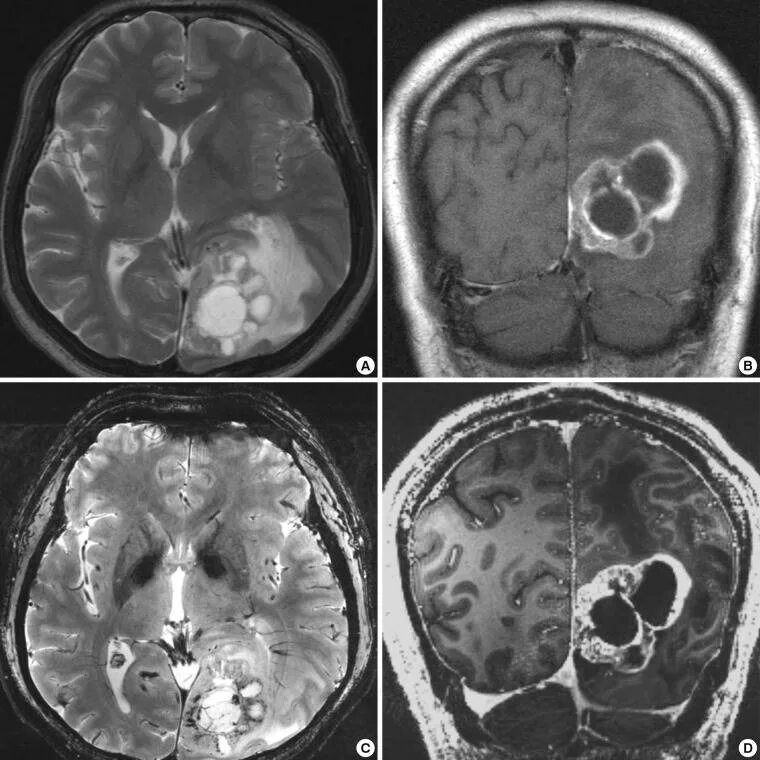

Компьютерная томография с болюсным контрастированием. Кт толстой кишки с контрастированием. Кт с болюсным контрастированием что это. Глиобластома мультиформная степень 4. Неоперабельная глиобластома головного мозга.. Глиобластома лобной доли мрт. Глиобластома злокачественная опухоль агрессивная.

Глиобластома мультиформная степень 4. Неоперабельная глиобластома головного мозга.. Глиобластома лобной доли мрт. Глиобластома злокачественная опухоль агрессивная. Филлоидная фиброаденома молочной железы УЗИ. УЗИ признаки доброкачественных опухолей молочных желез. Доброкачественная опухоль молочной железы на УЗИ. Опухоль молочной железы на УЗИ.

Опухоль шишковидного тела. Опухоль шишковидного тела в головном мозге. Пинеалома опухоль шишковидной. Опухоль шишковидной железы симптомы. Глиома внутримозговая кт. Метастатические опухоли мозга.

Глиома внутримозговая кт. Метастатические опухоли мозга. ПЭТ кт томограмма. Кт, ПЭТ И ПЭТ/кт. ПЭТ кт с контрастом. Скопление контраста ПЭТ кт.

Маммография молочных желез объемное образование. Опухоль молочной железы. Онкология молочной железы. Опухольмолочныйжелезы. Доброкачественная злокачественная опухоль головного мозга мрт. Глиома головного мозга мрт. Опухоль головного мозга на кт.

Доброкачественная злокачественная опухоль головного мозга мрт. Глиома головного мозга мрт. Опухоль головного мозга на кт. Карциноид червеобразного отростка гистология. Карциноид кишечника гистология. Карциноид червеобразного отростка патанатомия. Карциноидная опухоль микропрепарат.

Карциноид червеобразного отростка гистология. Карциноид кишечника гистология. Карциноид червеобразного отростка патанатомия. Карциноидная опухоль микропрепарат. Мрт головного мозга с контрастированием. Мрт с контрастированием опухоль. Мрт головы с контрастом. Магнитно резонансная томография с контрастом головного мозга.

Мрт головного мозга с контрастированием. Мрт с контрастированием опухоль. Мрт головы с контрастом. Магнитно резонансная томография с контрастом головного мозга. Классификация опухолей. Классификация новообразований. Классификация опухолей по воз. Классификация воз опухолей костей.

Классификация доброкачественных опухолей опухолей. Злокачественные опухоли классификация схема. Классификация доброкачественных и злокачественных опухолей. Классификация доброкачественных новообразований. Диагностические критерии глиомы головного мозга. Объемное образование головного мозга. Локализация опухолей головного мозга. Первичные и вторичные опухоли головного мозга.

Диагностические критерии глиомы головного мозга. Объемное образование головного мозга. Локализация опухолей головного мозга. Первичные и вторичные опухоли головного мозга.

Доброкачественная опухоль кости классификация. Классификация опухолей и опухолеподобных поражений костей. Классификация опухолей воз. Опухолеподобные заболевания костей. Глиобластома головного мозга мрт. Менингиома головного мозга мрт. Менингиома грейд. Опухоли мозга (менингиома);.

Глиобластома головного мозга мрт. Менингиома головного мозга мрт. Менингиома грейд. Опухоли мозга (менингиома);.